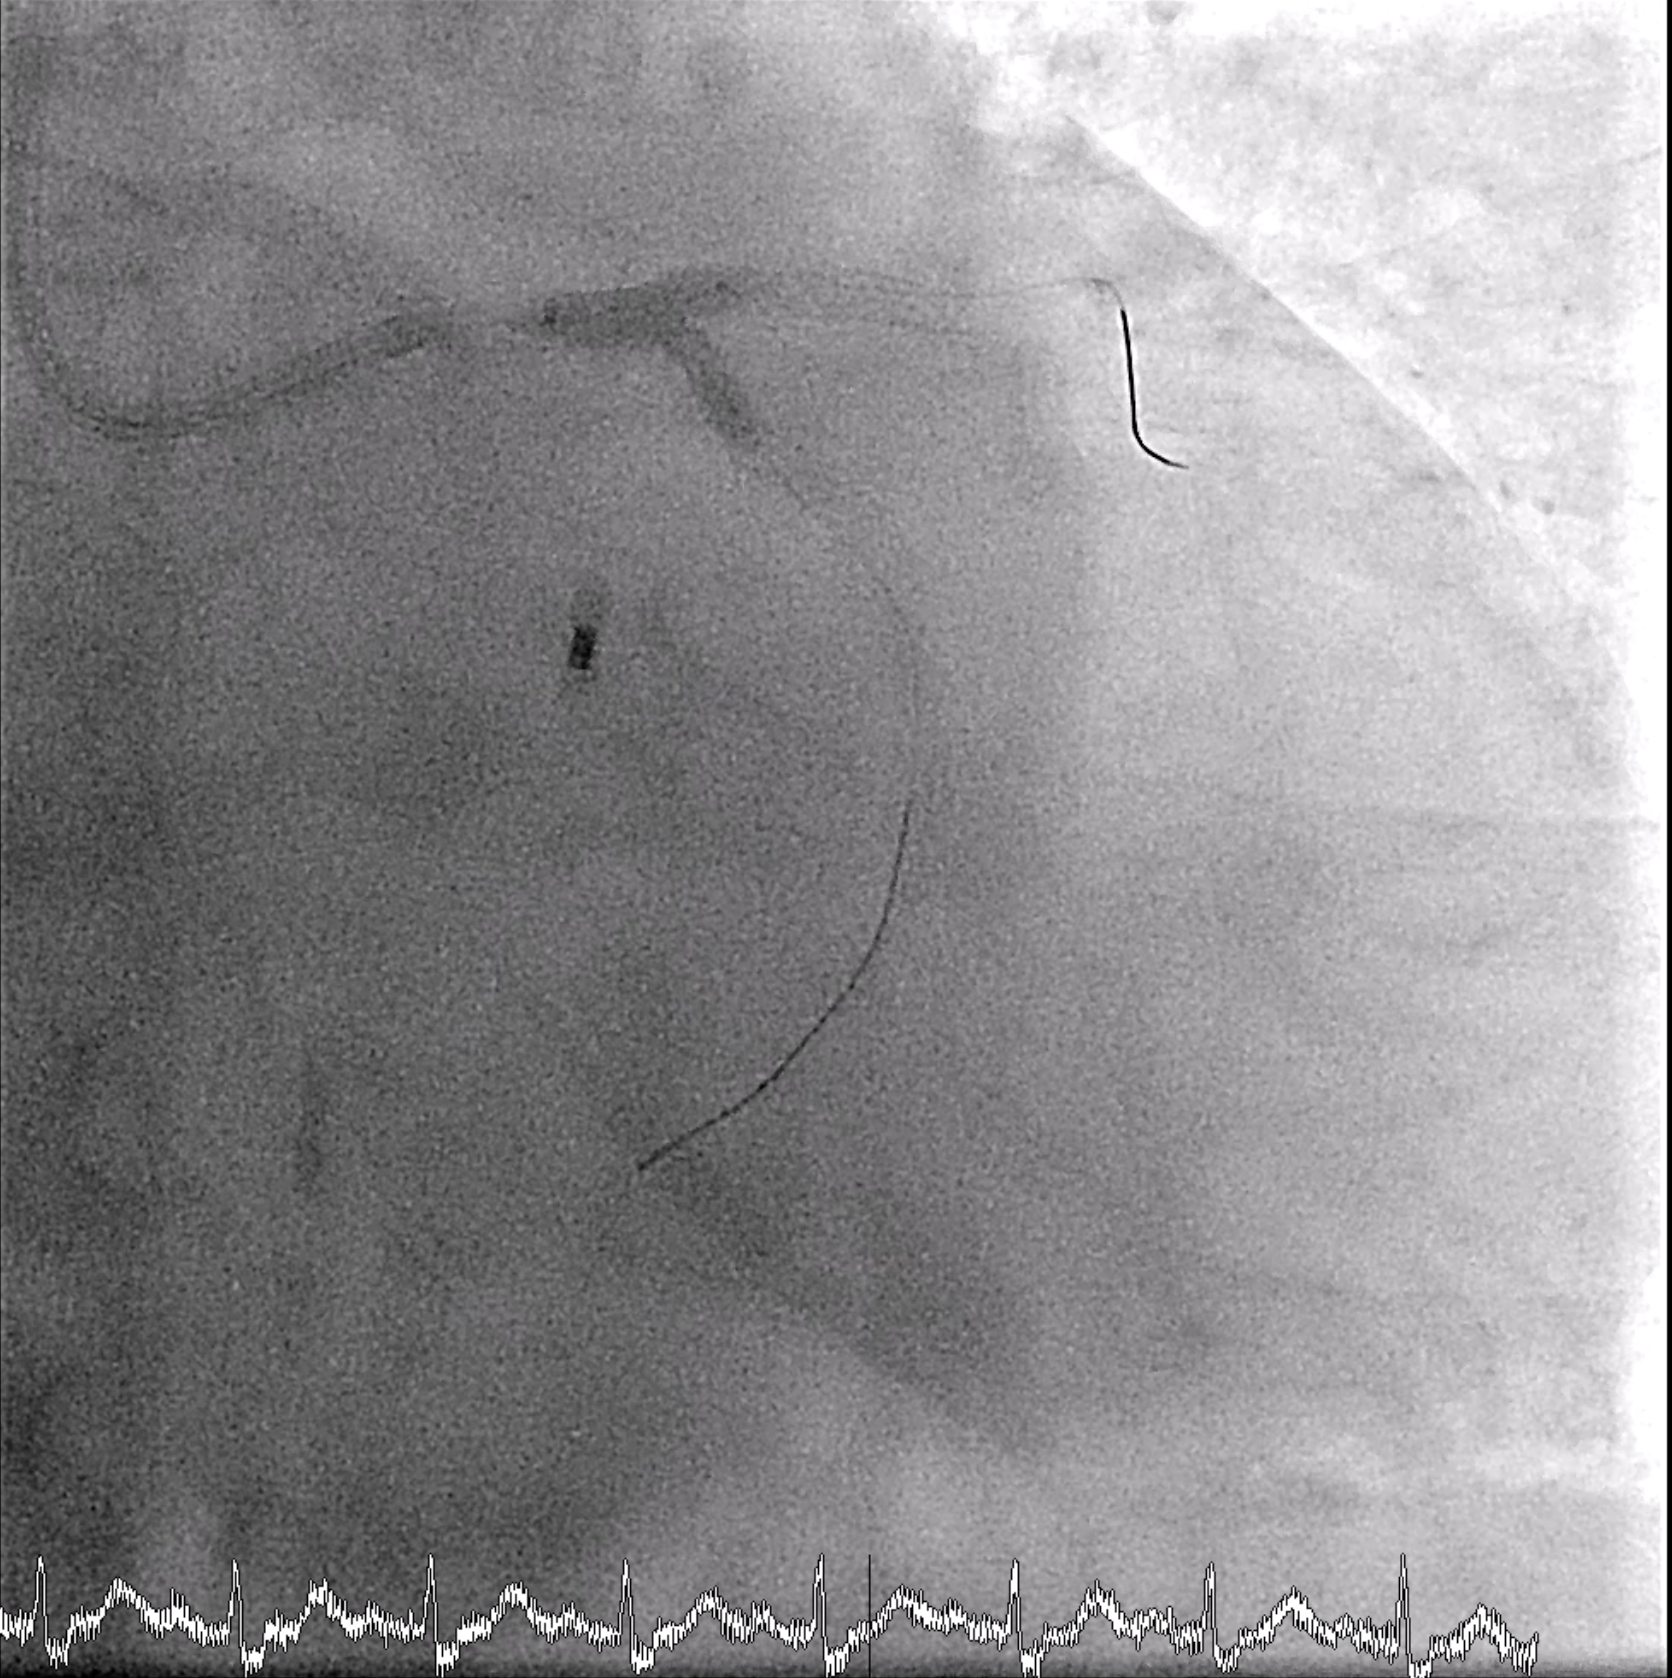

An 8 Fr IABP sheath was inserted via the right femoral artery under fluoroscopic guidance. The guidewire was advanced to the aortic root, and an ARROW IABP catheter was positioned in the descending aorta at the level of the aortic knob with good augmentation. Left femoral access was left for possible mechanical circulatory support. PCI was then initiated via right radial access using a 6/7 Fr APT sheath. The LMCA was engaged with an XB 3.5/7 GC, and an Anyreach wire was advanced to the LAD. IVUS could not cross the heavily calcified LM bifurcation, so rotational atherectomy was performed. After exchanging to a Rotadrive floppy wire, rotablation with a 1.75 mm burr was performed from LM to LAD for three runs at 147,000–166,000 rpm. POBA was carried out along LAD-D and LAD-P, followed by IVUS confirming circumferential calcification.Attention was then turned to the LCx. Due to uncrossable IVUS, the wire was exchanged for a Rotadrive floppy wire and rotablation was repeated from LM to LCx for seven runs at 136,000–166,000 rpm. Balloon dilation was performed, and IVUS again showed heavy LM–LCx calcification. A 3.0¡¿26 mm Frontier DES was placed from LM to LCx, followed by post-dilatation. Then a 3.0¡¿34 mm Frontier DES was deployed from LM to LAD-P, with sequential post-dilatation using NC balloons up to 18 atm. The bifurcation was optimized with rewiring and final kissing balloon inflation using 3.5 mm and 3.0 mm NC balloons, and proximal optimization with a 4.0 mm NC balloon.